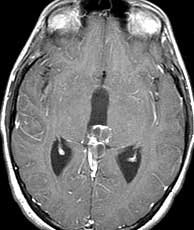

Diagnosis: Vein of Galen malformation

The VOG is the confluence of the basal vein of Rosenthal and the internal cerebral veins. It joins the inferior sagittal sinus to form the straight sinus. The vein of Galen malformation (aneurysm is a misnomer) is an abnormal developmental connection between the VOG and any of the following arteries; anterior cerebrals, anterior and posterior choroidals, lenticulostriates and thalamoperforators. It often presents in the neonatal period with CHF, cranial bruit or seizures. Treatment consists of endovascular embolization and/or surgery. The differential for this case without the angiogram is limited. Perhaps a huge calcified arterial aneurysm or pineal cyst could resemble this. A calcifying pineal region tumor is very unlikely due to the peripheral nature of the calcification. The angio however nails the diagnosis. Related Cases